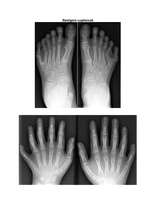

Jēdziens polidaktīlija jeb polidaktīlisms ir radies no grieķu valodas vārdiem „polus” (πολύς), kas nozīme „daudz” un „daktulos” (δάκτυλος), kas nozīmē „pirksts”. Polidaktīlija ir iedzimta anomālija, kas izpaužas kā vairāk nekā piecu pirkstu izveidošanās rokām vai kājām. Šī slimība tiek saukta arī par hiperdaktīliju. Kad plaukstai vai pēdai ir seši pirksti, tad to mēdz saukt arī par seksdaktīliju, heksadaktīliju vai heksadaktīlismu.

Papildus pirksts parasti ir mazs gabaliņš no mīkstajiem audiem, dažreiz tajos var būt arī kauli bez locītavas, retos gadījumos šie pirksti var būt arī veseli un funkcionējoši, daudz neatškiroties no pārējiem pirkstiem. Papildus pirksts visbiežāk sastopams plaukstas pusē, kur atrodas mazais pirkstiņš, tomēr dažreiz arī blakus īkšķim, retāk šī anomālija sastopama trīs vidējo pirkstu starpā.

Vairumā gadījumu papildus pirksts ir atzarojums, kas iziet no kāda no pārējiem pirkstiem, retāk šie papildus pirksti ir tieši piesaistīti plaukstas locītavai, tāpat kā pārējie pirksti.

Polidaktīlija izveidojas bērnam jau pirms dzimšanas attīstības periodā. Parasti pirksti no locītavām iziet normāli, bet pirkstu galos kauls sāk sadalīties vairākās daļās, radot no viena pirksta divus vai pat vairākus pirkstus. Parasti šī slimība tiek pārnēsāta gēnos, taču ir arī gadījumi, kad polidaktīlijas iedzimšana nav izskaidrojama. …